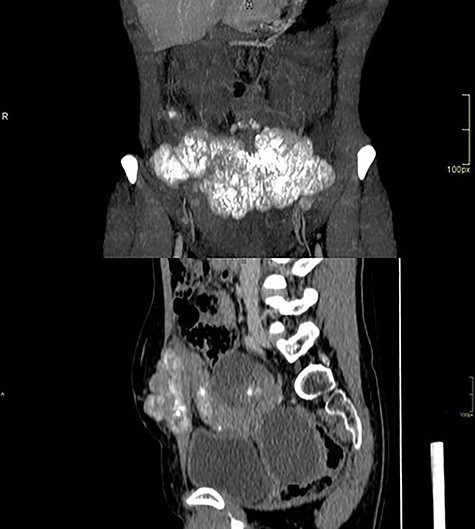

Computed tomography of the abdomen showed solid-cystic lesions in the pelvis (Fig. 2) and a massive expansive lesion in the AW, with soft tissue density and a volume of 334 cm3 (Fig. 3). Between the AW and the pelvic lesions, formation with soft tissue density, heterogeneous enhancement and calcifications are identified, measuring 12.5 × 2.5 cm in the major latero-lateral and anteroposterior axes, compatible with ‘omental cake’.

CT with heterogeneous solid-cystic lesions with contrast enhancement, septations and gross calcifications, in the topography of the uterine attachments, measuring 5.8 × 4.9 × 5.0 cm on the right (74 cm3 volume), 7.8 × 8.7 × 7.9 cm (278 cm3 volume) in the region of the rectouterine pouch and 2.9 × 2.4 × 2.3 cm (8.3 cm3 volume) in the left adnexal region.

Abdominal wall CT with expansive lesion with soft tissue density, heterogeneous, with the appearance of a cluster of nodules, measuring 16.4 × 5.1 × 7.7 cm (334 cm3 volume) in the major latero-lateral, antero-posterior axes and longitudinal, respectively.